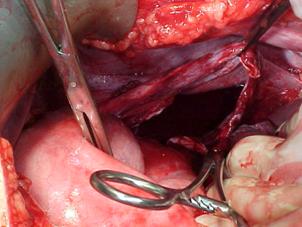

Plaga impuscata in

regiunea poplitee Leziune de artera

poplitee

Sectiune de artera

poplitee Refacerea traiectului vascular cu grefa venoasa